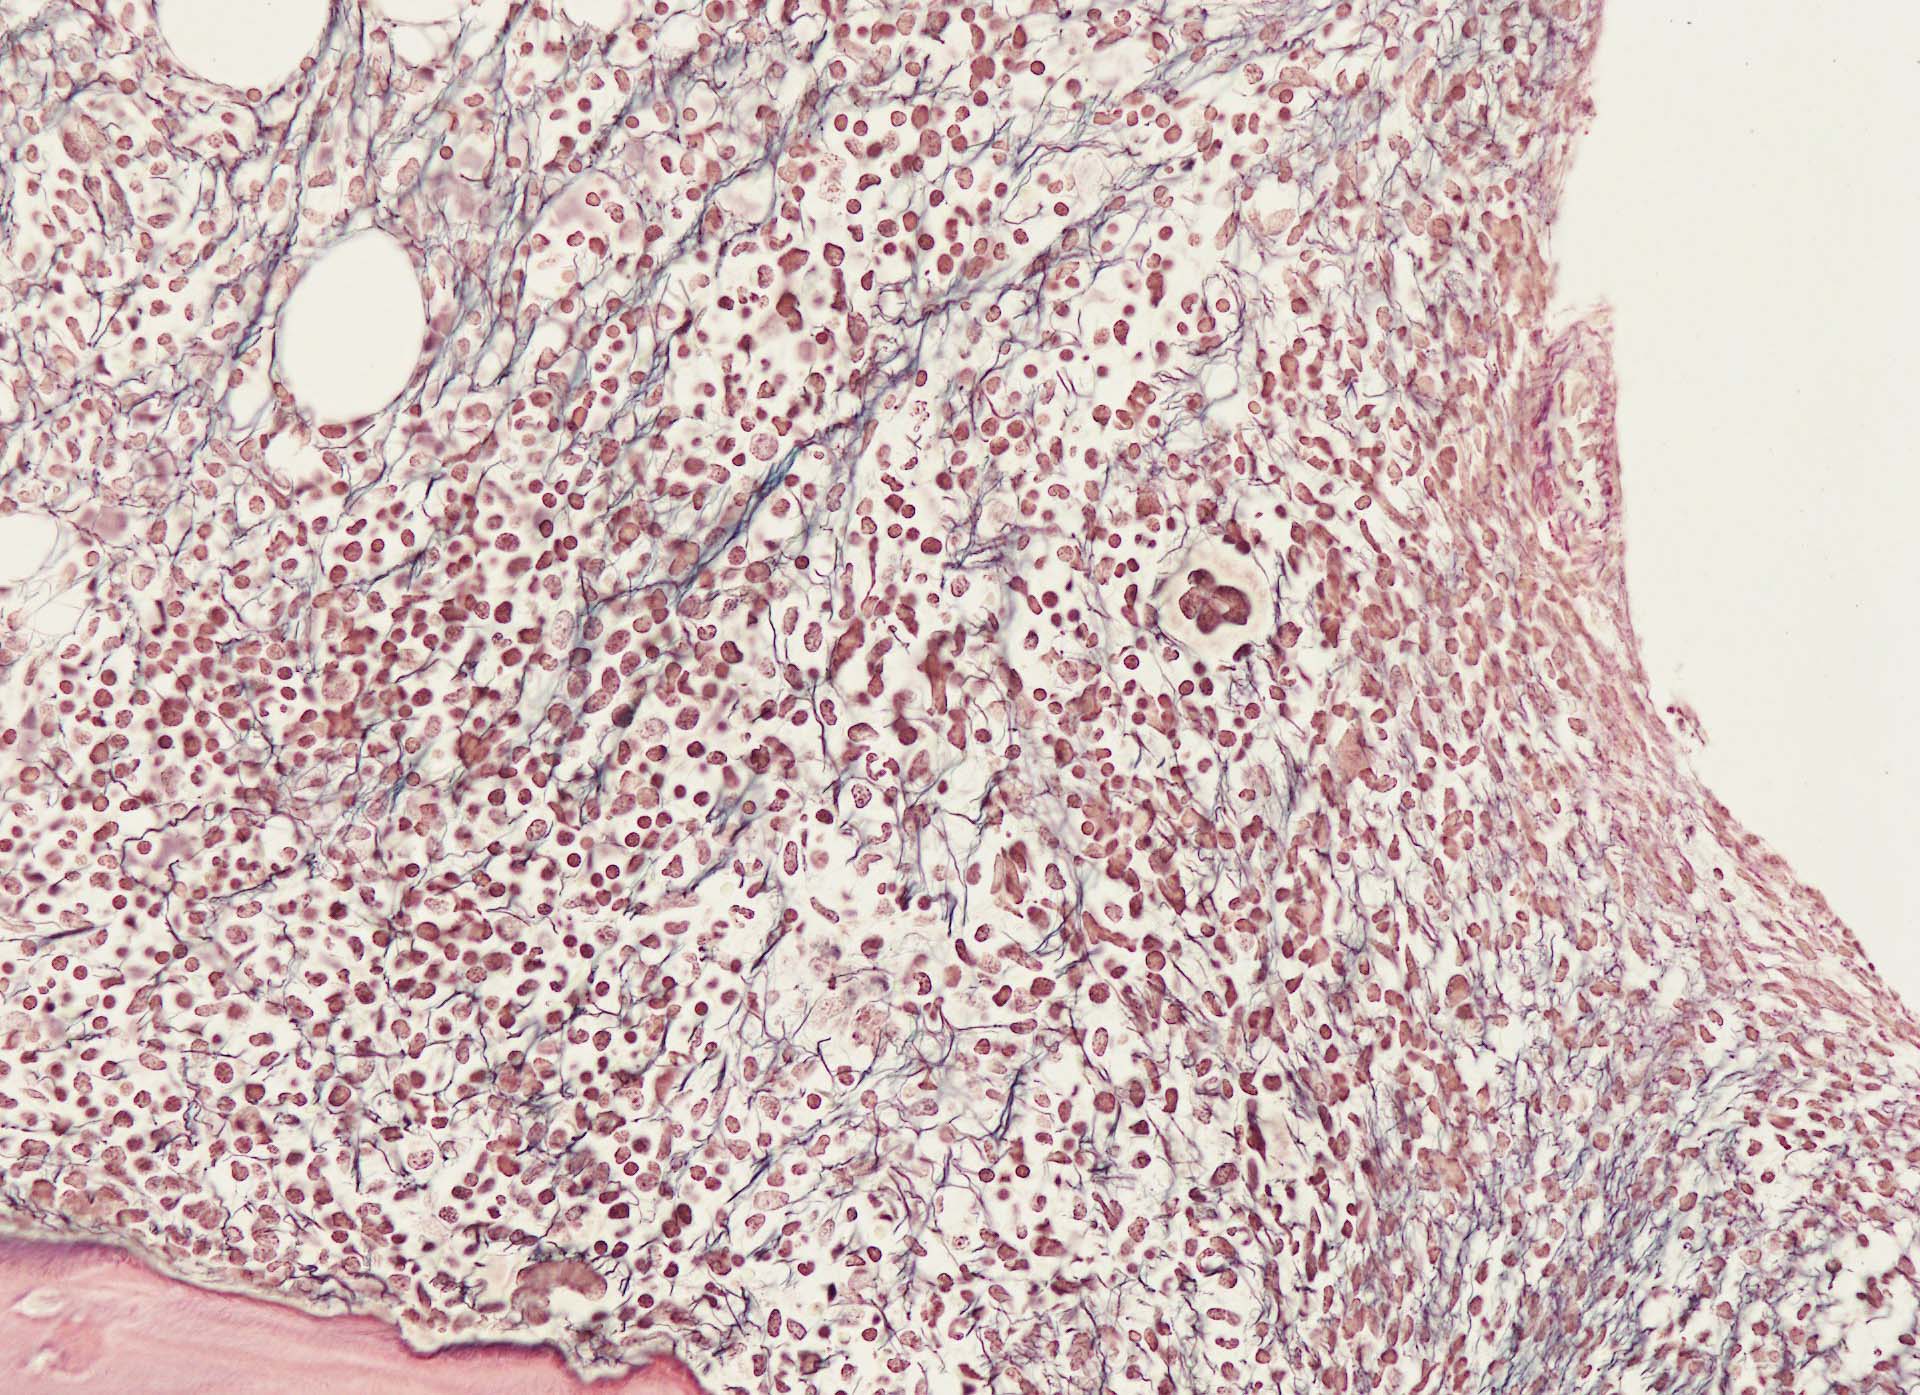

Hairy-FCM のコピー.jpg ASD-up-PAX5ok.jpg びまん性にPAX5陽性の小型B-cellsが増殖している.

増殖細胞はCD20(相変わらずべったり染まる), CD19, PAX5陽性 CD25陽性.

BRAF V600E変異タンパクの免疫染色(山梨医大 大石先生に染色していただきました. ベンタナ, Optiview)